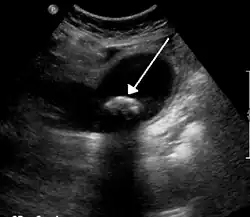

Une colique hépatique (une douleur qui n'a rien de colique et rien d'hépatique, le nom plus approprié étant "douleur vésiculaire") est un symptôme douloureux ressenti par un patient dans la partie supérieure droite de l'abdomen. Cette douleur est généralement isolée ; elle ne s'accompagne pas de fièvre, d'altération de l'état général ou d'ictère. Elle peut s'accompagner d'une fièvre et d'un ictère dans la triade de charcot ou de villard. C'est une douleur généralement déclenchée par un repas riche en graisse (entrainant une augmentation de la CCK --> contraction vésicule biliaire).

On retrouve ce symptôme, par exemple, lors de l'expulsion d'un calcul hors de la vésicule biliaire (en même temps que la bile), lors de la contraction de celle-ci. Le calcul provoque une douleur vive en se déplaçant dans les voies biliaires : cette douleur peut irradier jusqu'aux côtes et l'épaule du côté droit.